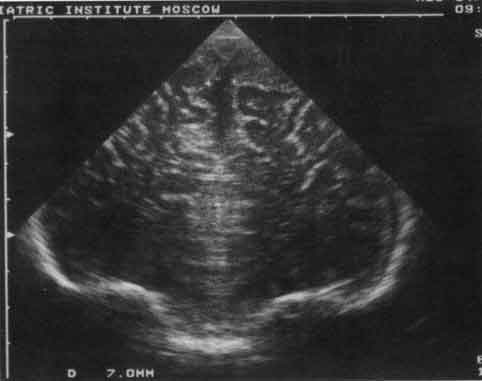

Таким образом, для СМ и рахита типично только умеренное расширение межполушарной щели, а для ГГС - умеренное расширение боковых и III желудочков, увеличение ИР. Увеличение межполушарной щели без сопоставления с данными анамнеза и клиники не является ультразвуковым критерием наружной гидроцефалии (рис. 1, 2).

Рис. 1. Эхограмма лобных долей мозга грудного ребенка при семейной

гидроцефалии.

Маркерами обозначена расширенная межполушарная щель.